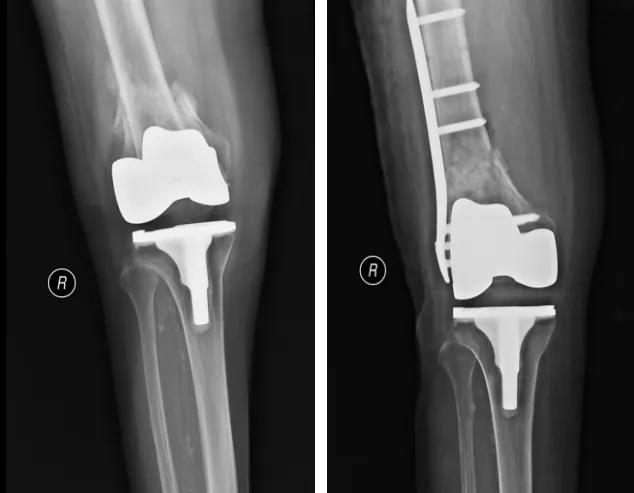

膝关节外科技术力量雄厚,科室配备医护人员30人,其中,主任医师5名,副主任医师3名,主治医师3名,住院医师4名,博士1名,硕士研究生4名。开放床位48张。该科擅长对膝关节严重创伤(包括股骨远端骨折、髌骨骨折、胫骨平台骨折等)、膝骨关节炎阶梯化治疗、保膝治疗、膝关节微创单髁置换术、全膝关节置换术、膝关节翻修术具有丰富的临床诊疗经验,追求微创、无痛、快速康复。对膝关节骨性关节炎采取阶梯化治疗方案,坚持中西并重、内外兼治的原则,取得满意的治疗效果。早期利用中医中药的传统优势,使用中医外治法,例如烫熨治疗、中药涂擦、雷火灸、中药塌渍等,同时辩证内服本院中药制剂及内服方药以及配合西药治疗,开展健康教育,运用运动疗法、物理治疗等辅助支持;中期开展软骨修复、截骨术、单髁置换术、髌股关节置换术等;对于终末期的膝关节OA采用全膝关节置换术。【膝关节外科主要特长】 (一)膝骨关节炎高位截骨术

(二)膝骨关节炎单髁置换术

(三)膝骨关节炎全膝关节置换术

(四)膝关节置换术后关节翻修术